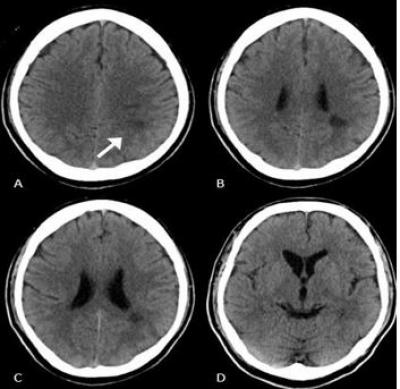

Stroke Presented as Gerstmann Syndrome

Article |

June 28, 2022 - 3:57pm

| By

Siti Nur Izni SMA

,

Kevin WCS

AHMAD KHALDUN I

Related Terms:

emergency

Gerstmann syndrome

stroke

Case report

kecemasan

sindrom Gerstmann

strok